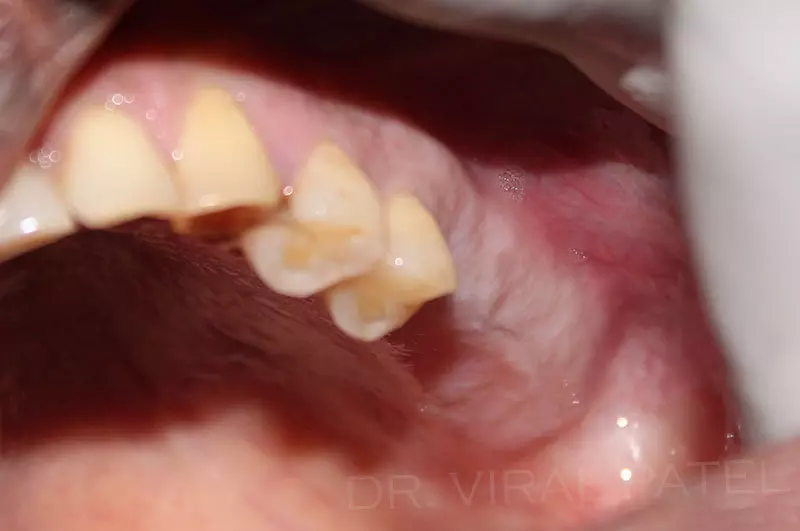

Dental Implant India are the most recent and advanced form of dentistry through which new teeth can be replaced without damage to the teeth and feels absolutely natural.

Implant surgical technique is a highly specialized & skillful form of dentistry which combines all the skills & knowledge of periodontics, prosthodontics & oral surgery.